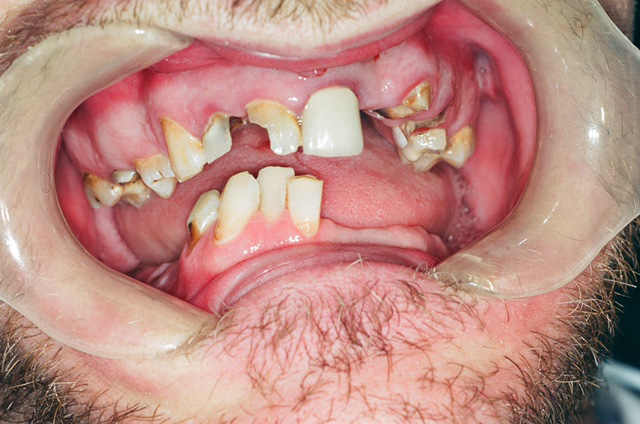

During the clinical exam, I identified that the patient’s pain was originating from the maxillary right first premolar. This tooth was fractured, had pulpal involvement and a periapical lesion, and was non-restorable (Fig. 2). The patient had generalized decay, gingival recession and attrition throughout her mouth. Although the caries was not blackened, the decay pattern (Class V anterior lesions and coronal fractures) was consistent with methamphetamine abuse (Fig. 3).

Fig. 2 Fig. 3